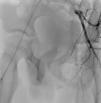

Con partículas hemostáticas, se realiza embolización superselectiva de las mismas, comprobándose el cese del extravasado (fig. 3). Se da de alta a las 24 h del procedimiento. En el control posterior, un mes después el paciente refiere erecciones matutinas con normalidad.